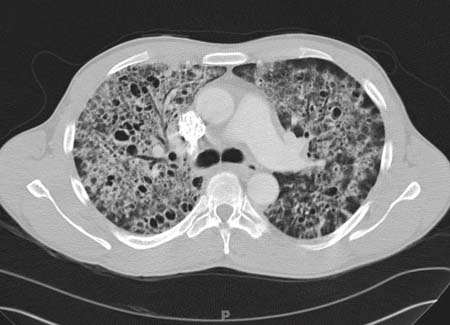

Pneumocystis jirovecii pneumonia

Computed tomography scan of the thorax showing bilateral pulmonary interstitial infiltrates and pneumatoceles (cysts), which are typical of Pneumocystis pneumonia (PCP)

From the collection of Matthew Gingo, UPMC